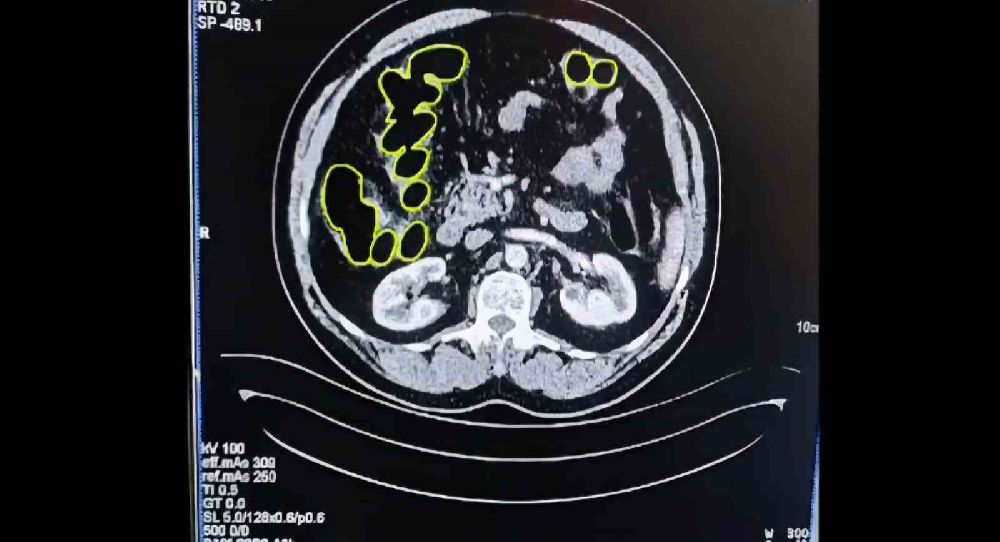

Şüphelilerin Kayseri Şehir Hastanesinde iç beden muayenesine alınırken, mide ve bağırsaklarında da çok miktarda kapsül şeklinde uyuşturucu olduğu değerlendirilen yabancı maddeler tespit edildi.